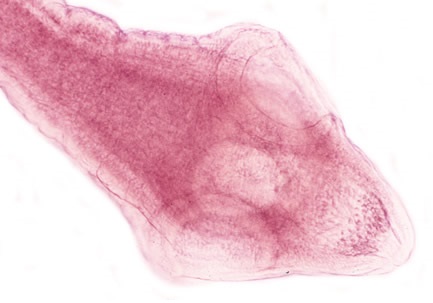

Sán trưởng thành có màu hồng nhạt, kích thước trung bình dài từ 10 - 70 cm; có khoảng 175 đốt hình elíp hoặc đốt dài.

Đầu có hình thoi, kích thước 0,25 - 0,5 mm, có 4 đĩa hút hình chén. Vòi có hình gậy, miệng của vòi mang 1 - 7 hàng răng (móc), số hàng răng phụ thuộc vào tuổi của sán, có thể nhô ra hoặc thụt vào.

Những đốt ở gần đầu ngắn và mảnh, rộng khoảng 0,2mm; những đốt sán chưa trưởng thành gần cổ thì chiều rộng hơn chiều dài và dần trở nên vuông hơn khi trưởng thành ở phần giữa và già ở phần cuối; đốt già có kích thước 27 x 12mm có chứa trứng; mỗi đốt sán trưởng thành và già chứa 2 cơ quan sinh dục đực, cái và hai lỗ sinh dục nằm 2 bên của đốt sán. Tinh hoàn của các đốt sán trưởng thành có 100 - 200 nang trứng; mỗi nang trứng chứa từ 8 - 15 trứng. Buồng trứng đã có tuyến noãn hoàn; tử cung phát triển giống hình mạng lưới.

Trứng có vỏ mỏng, hình cầu, kích thước trung bình 35-40mm, có phôi sán chứa 3 đôi móc.

Hình 1:Sán trưởng thành | Hình 2:Đầu sán | |